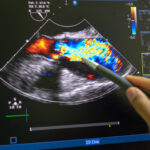

With the ultrasound renal denervation procedure, doctors insert a catheter into the leg or wrist of the patient to reach the kidneys. Therapy allows doctors to disrupt signals in the renal arteries, thus helping to lower blood pressure as a result. While the procedure is invasive, most patients in the study were discharged the same day, per the press release.